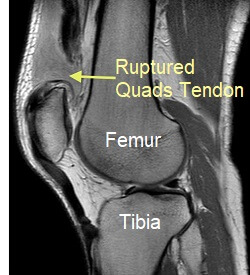

A quadriceps tendon rupture is a rare but serious knee injury.

With a quads tendon tear, the tendon that connects the quadriceps muscles at the front of the thigh to the kneecap (patella) tears

You doctor may send you for x-rays, ultrasound or an MRI scan if there is any uncertainty about the injury, or to confirm whether there is a partial or full quadriceps tendon rupture.